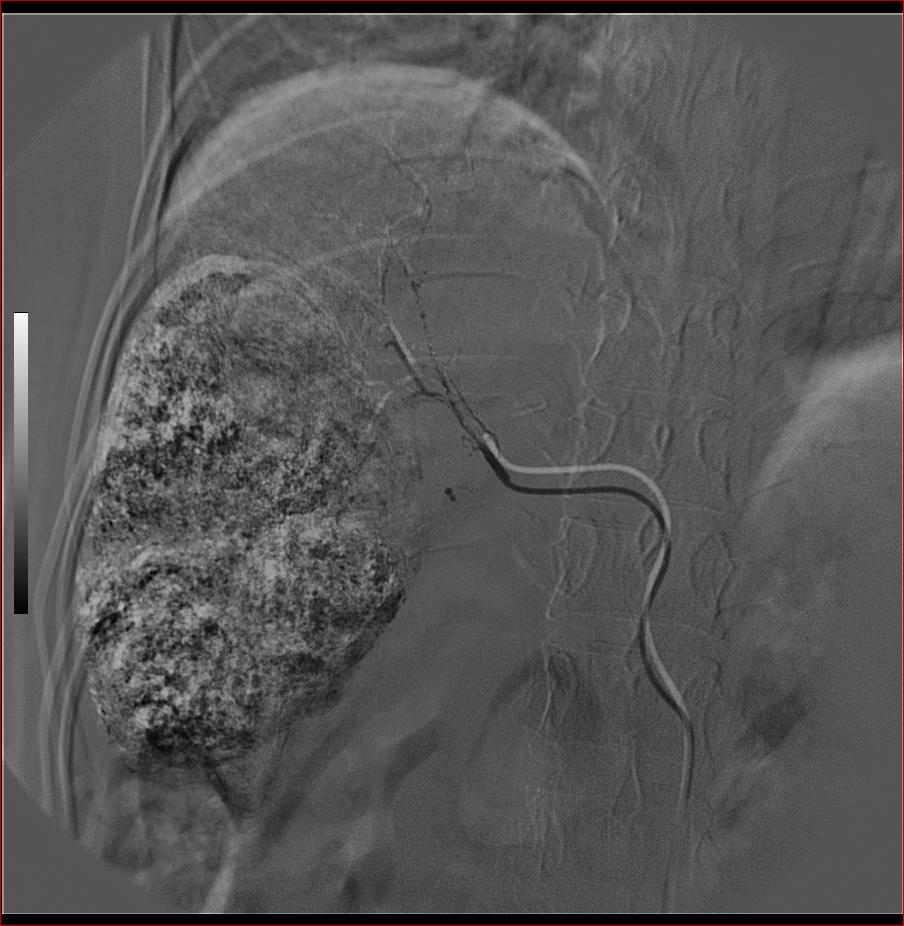

第二次(50天后)

栓塞的非常理想。

好牛的,右肝动脉发自肠系膜上动脉,不用微导管分次进行末梢栓塞,肿瘤染色完整。再次学习了。